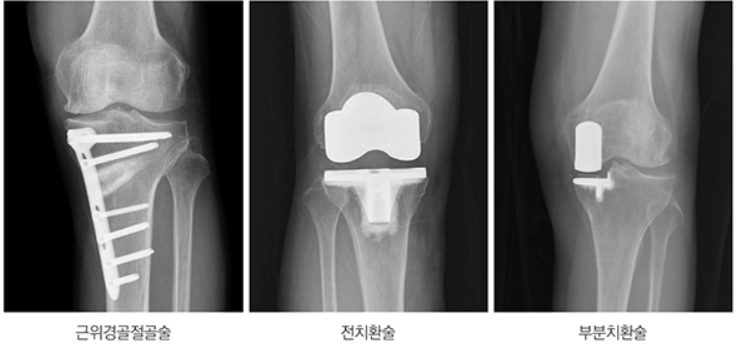

비수술적 치료에 반응이 없고, 통증이 심한 경우 연골재생술, 관절경수술, 인공관절 부분치환술 혹은

전치환술까지 고려합니다.

⚑ 연골재생술

정의: 연골재생술은 손상된 연골을 복원하는 여러 종류의 수술적 치료를 아우르는 용어입니다. 대표적으로 줄기세포를 이용한 연골재생술(예: 카티스템)이 존재합니다.

방법: 연골재생술은 손상부를 관절경이나 절개로 노출한 뒤, 연골결손 부위에 제대혈 유래 혹은 골수 유래 줄기세포를 이식하는 ‘수술’입니다.

시술에 비해 더 적극적으로 연골 손상 부위를 정리하고 줄기세포가 연골에서 잘 자리잡게 보조물질과 함께 이식합니다.

범위와 효과: 크거나 심한 연골 결손, 또는 중등도 이상의 경우에 적용됩니다. 수술적 개입으로, 연골결손부위에 줄기세포를 확실히 고정하여 보다 효과적인 재생을 유도합니다. 노년층, 넓은 결손 등 난이도가 높은 경우에도 적용됩니다.

3. 말기(4기) 관절염 치료

♦ 주요 증상: 통증이 극심하며, 밤에도 불편, 뼈와 뼈가 직접 맞닿는 엑스레이 소견.

♦ 주요 치료법:

인공관절 수술: 연골이 거의 남지 않고 보존적 치료에 반응이 없는 경우 시행. 최근 로봇 인공관절도 도입 중.

수술 전 최대한 연골 보호: 가능하면 연골 재생술 등 보존적 치료를 적용하나, 효과가 없으면 수술적 치료로 전환.

수술 후 재활: 물리치료와 운동 병행.